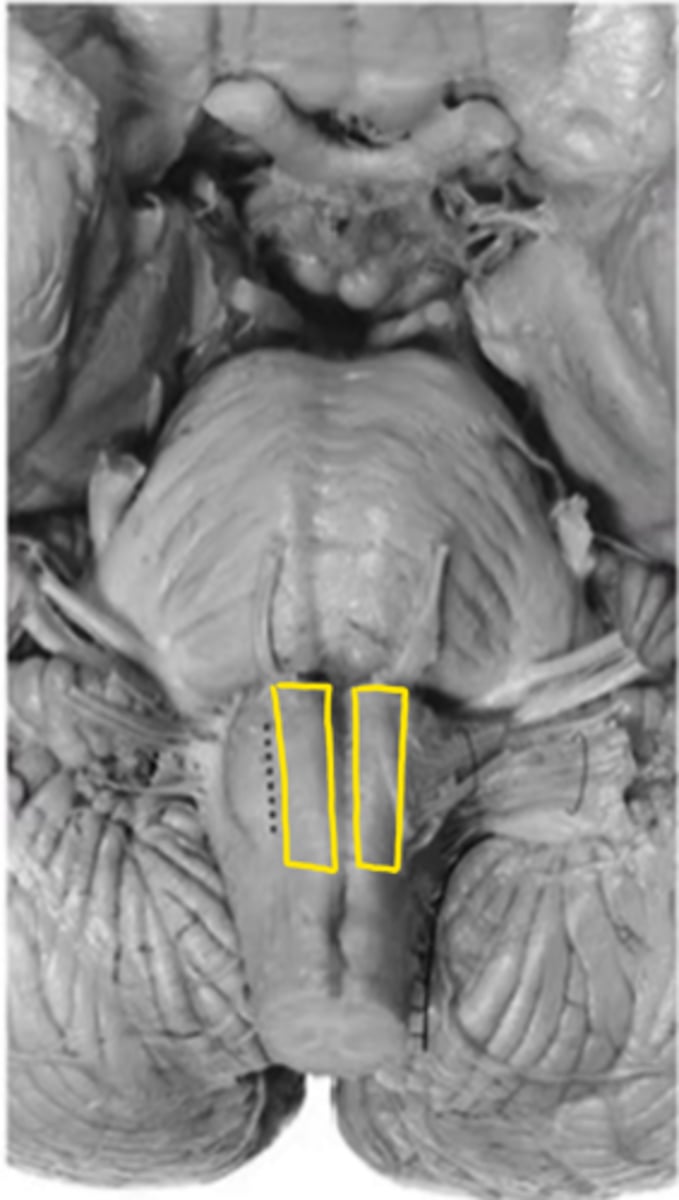

medullary pyramids

ID the structure

anterior median sulcus

open medulla

ID the brainstem level